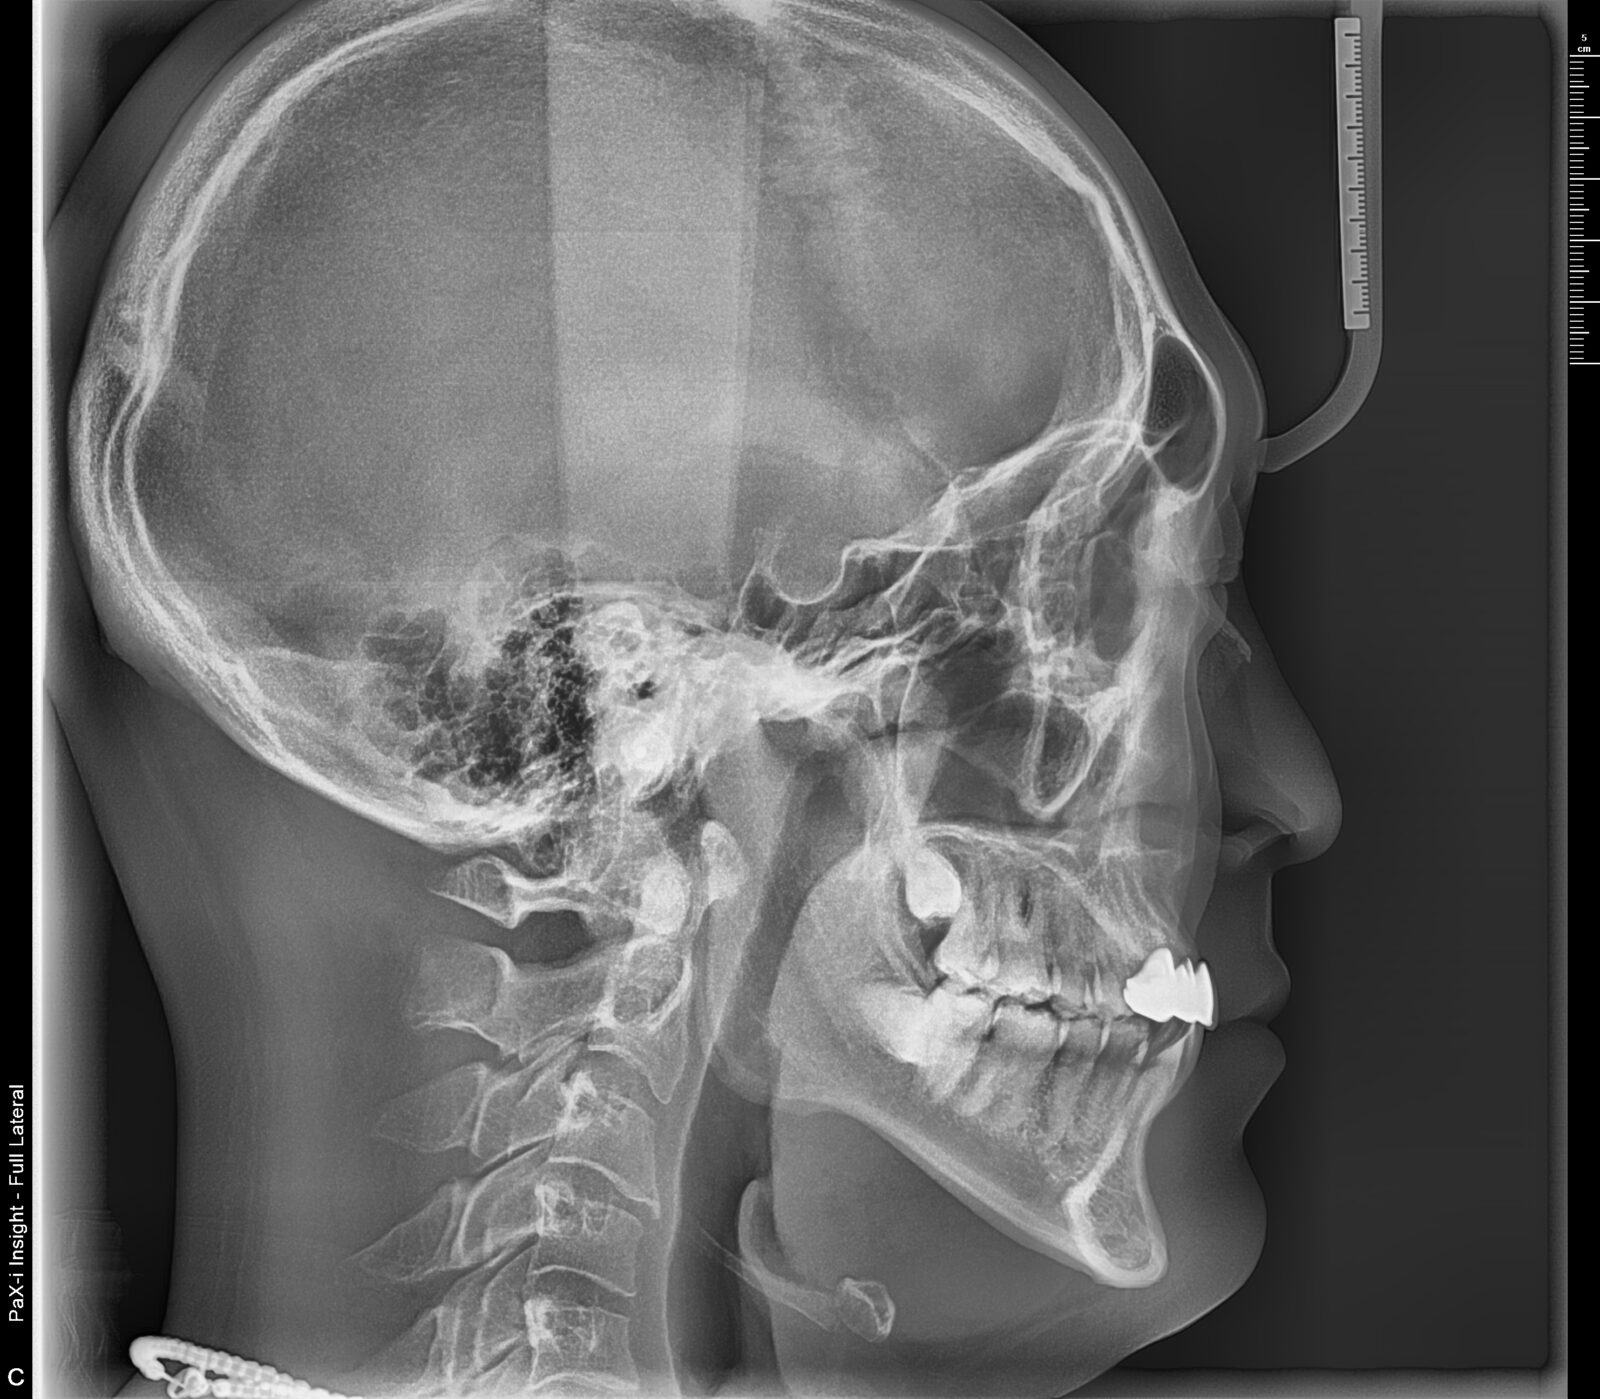

リテーナー不使用と、定期メンテナンス通院中止による後戻りの改善の症例

正中も揃った。ワイヤー矯正前の歯列は前歯が出ていたとのこと。

上顎前歯の唇側の骨の厚みを確保すると安定してくるが、側方への外力をコントロールし、適度な垂直圧が維持される必要がある。

舌癖や、舌のポジションを含む習癖や習慣的な体の使い方の工夫が必須。

コンパクトな費用のプランを選択されたため出来なかったが、本当は6番、7番も微修正したいところ。

主訴は前歯だったが、小臼歯まで移動範囲に加えてバランスを整えていった。

定期メンテナンスの際に姿勢を含む習癖の改善のアプローチを行なった。

初診時と比較し、自然と骨格のズレも修正されていった。

首の歪みも確認できるようになった。

過去、非抜歯ワイヤー矯正をしたが、リテーナー不使用等による後戻りを改善したいとの要望に応える。

・費用:456,500円(税込) ※リテーナー別途

・治療期間:7ヶ月 (ステージ数:上顎9、下顎13+追加アライナー上顎9、下顎11)

・使用装置:インビザラインGO

・女性

・オプション:エアフロー